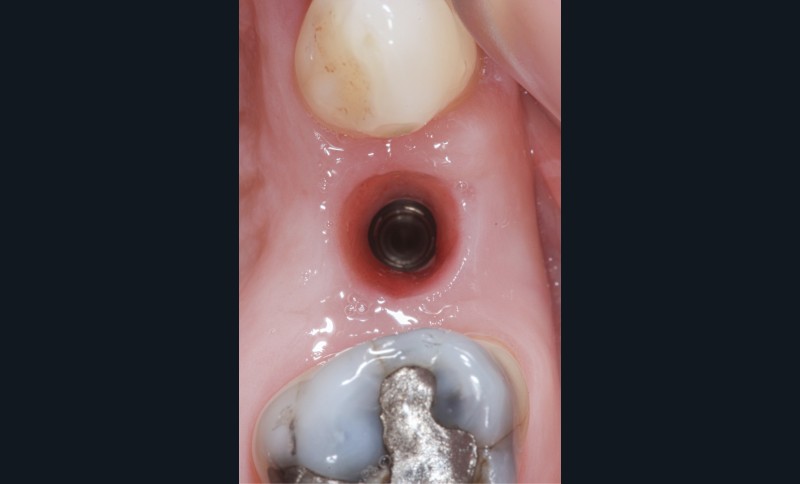

Sur une dent naturelle, le profil d’émergence est la zone de transition entre la racine et la couronne dentaire. En prothèse implantaire, le profil d’émergence se définit comme le contour des éléments prothétiques personnalisés et adaptés à l’architecture gingivale péri-implantaire (fig. 3). Le problème est que les racines dentaires, à la différence des implants qui les remplacent, ne sont pas de section ronde [5]. Les différentes vis de cicatrisation ne permettent pas d’obtenir un profil d’émergence proche de la réalité.

La conception de la partie transgingivale des prothèses répond maintenant à un consensus (profil concave dans la zone profonde dite subcritique, profil convexe au niveau du sulcus marginal, aussi appelé zone critique). Une augmentation du volume prothétique de la zone critique entraînera une récession des tissus péri-implantaires, une diminution de volume de la zone subcritique entraînera…